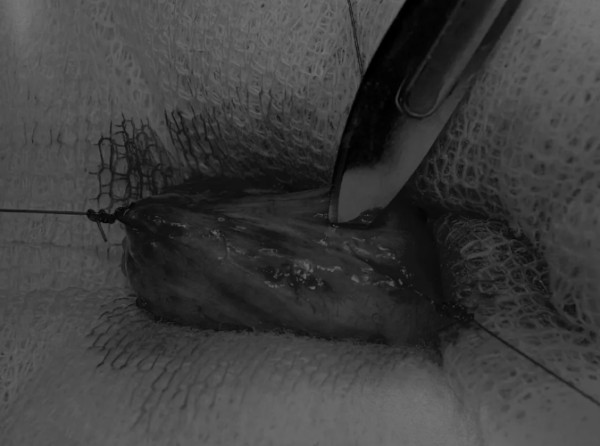

完成膀胱内冲洗后,应通过导尿管反向冲洗膀胱;砂样结石和血块会被冲到切口表面(图5)

图5 通过导尿管注入无菌生理盐水反向冲洗,可以去除微小的结石(箭头)和夹杂在膀胱黏膜皱褶中的砂样结石,以及可能在手术中形成的血块